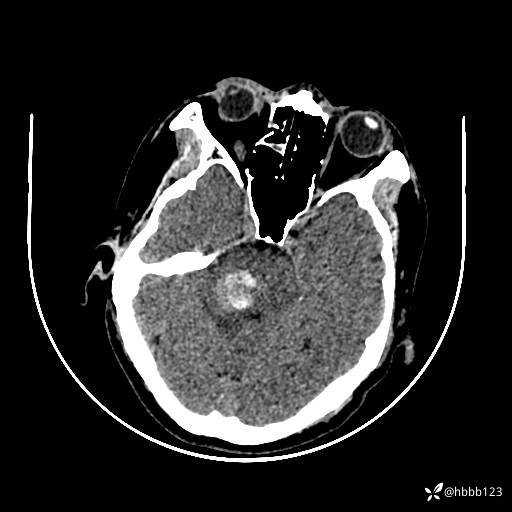

患者男,51岁。

简要病史:患者自述于1周前至某人民医院发现脑干肿瘤(具体不详),为求进一步诊断至我院就诊。

完善颅脑MRI平扫+增强,颅脑CT平扫:

颅脑CT平扫: